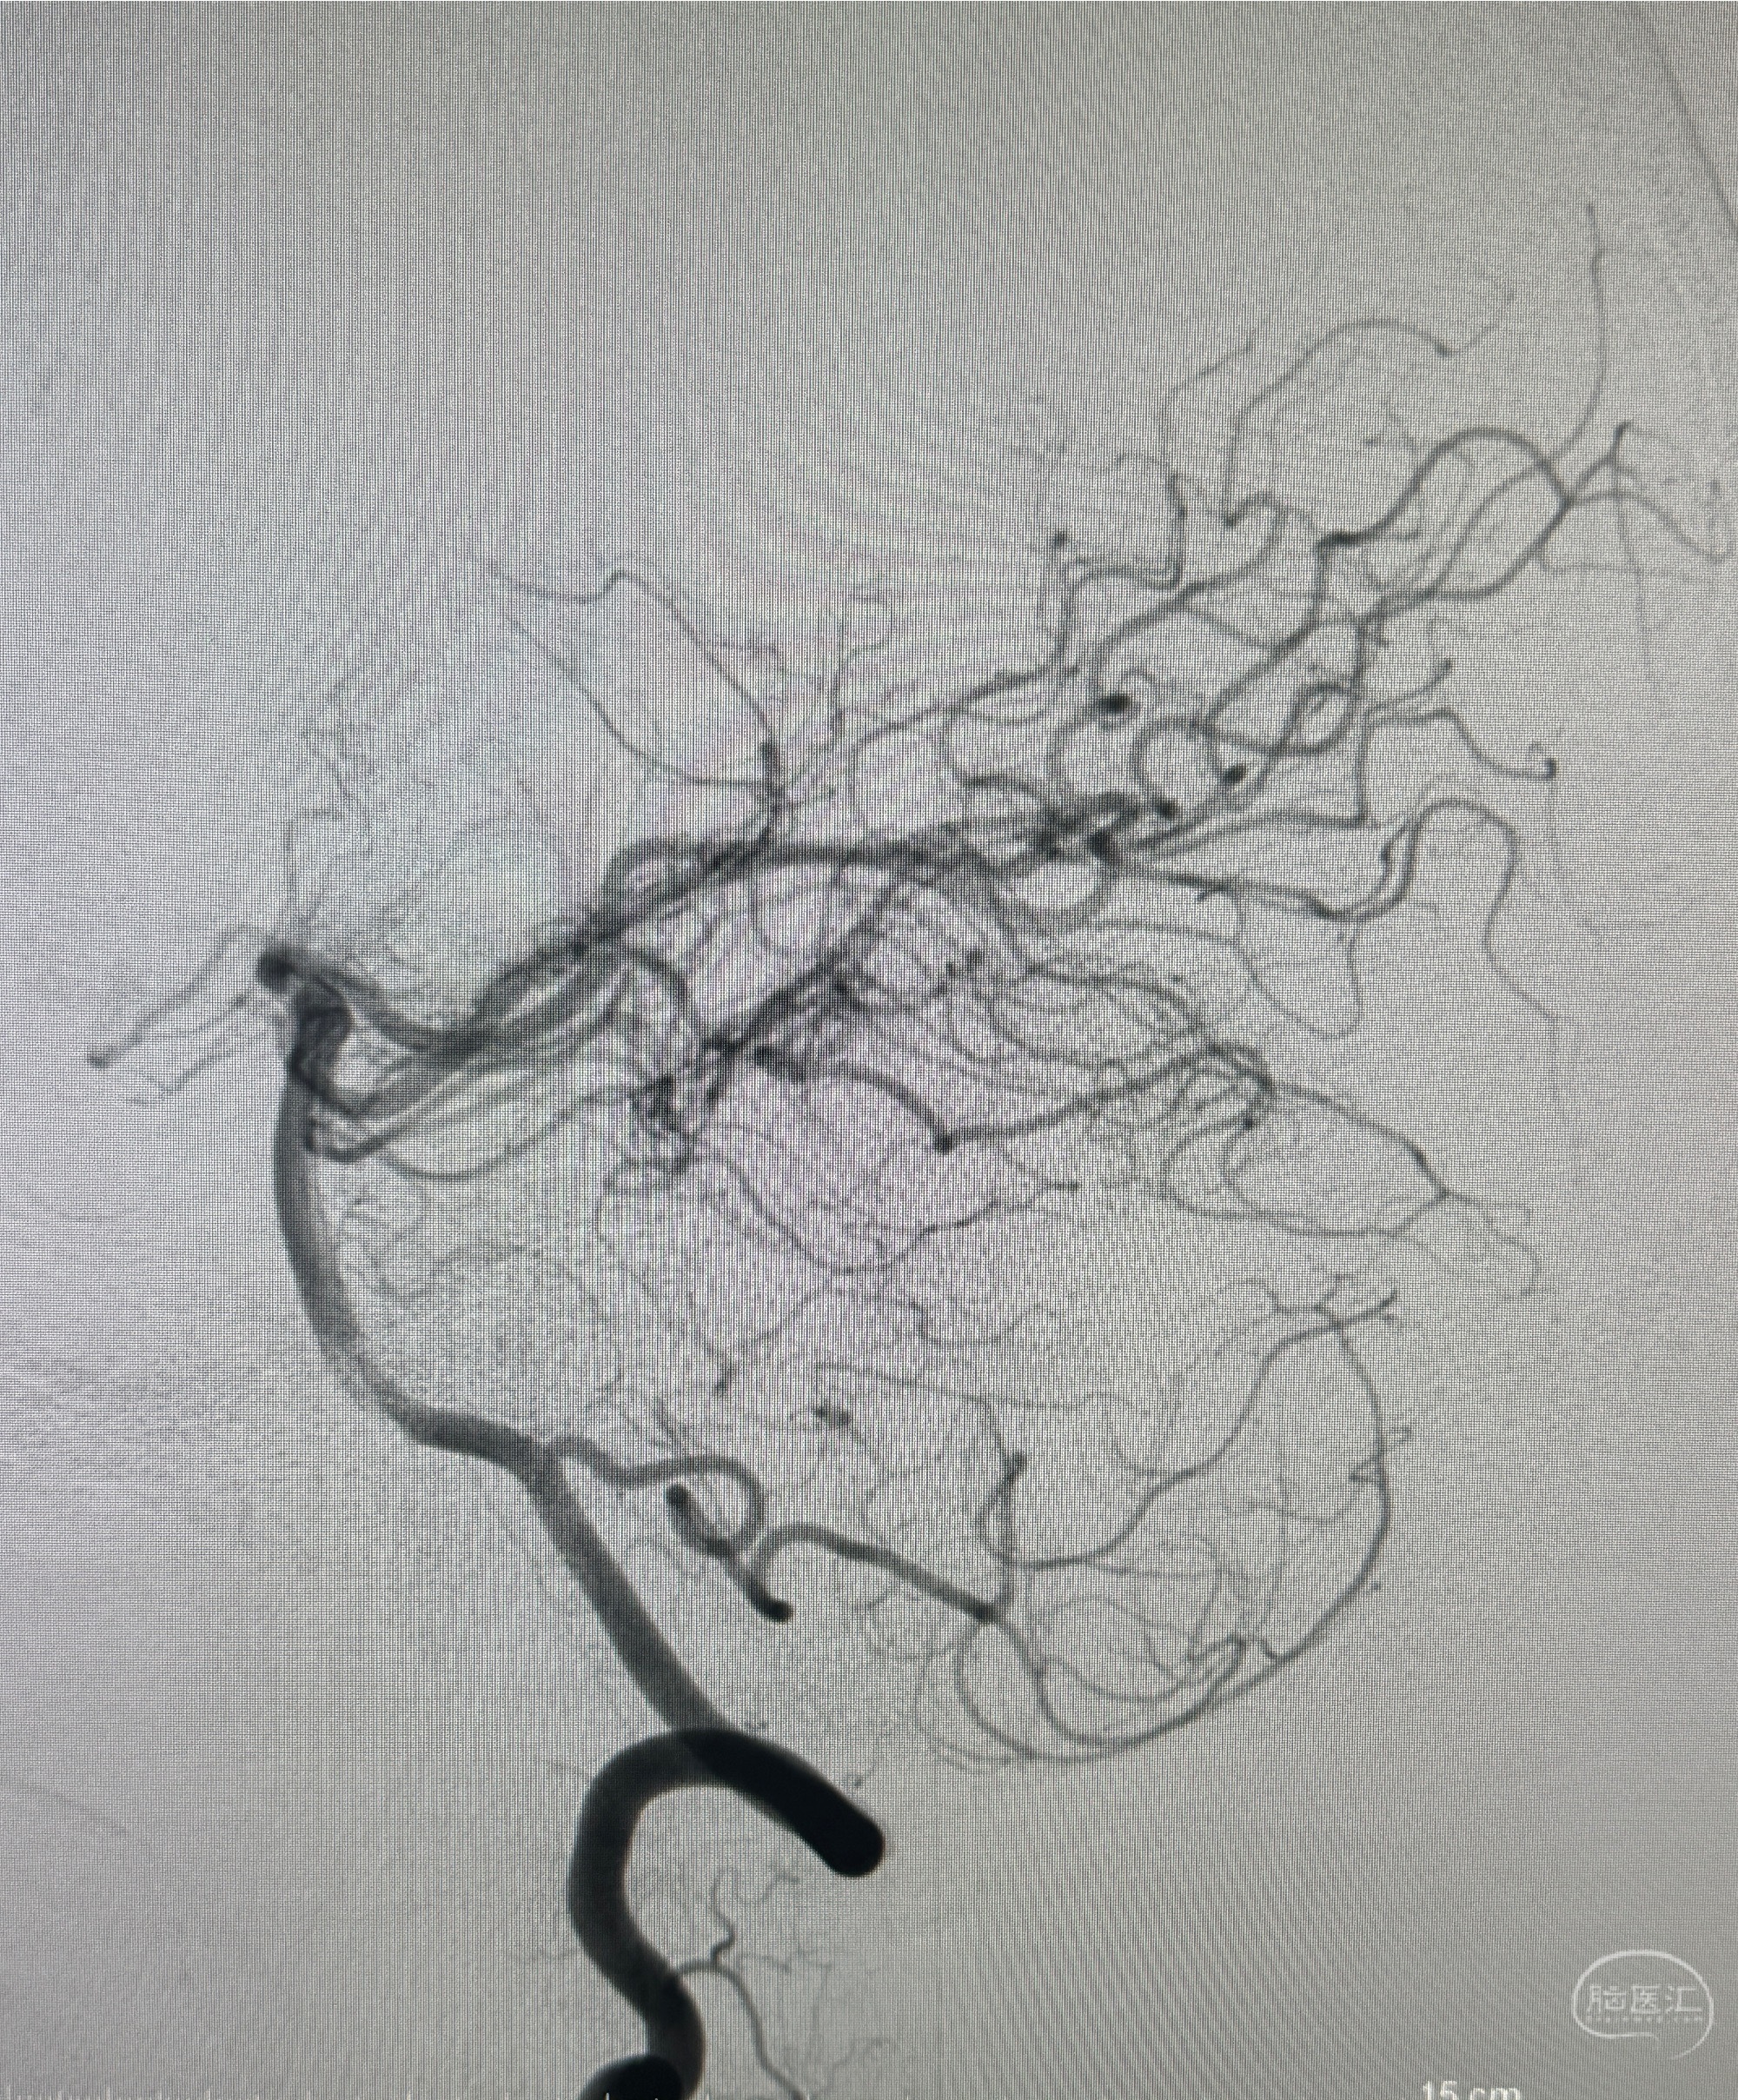

2023.07.12 江苏省泰州市人民医院在局麻下行脑血管造影提示左侧C5段动脉瘤(3.44*3.93mm)。

2023.07.24DSA+全麻下颅内动脉瘤密网支架+弹簧圈辅助干预